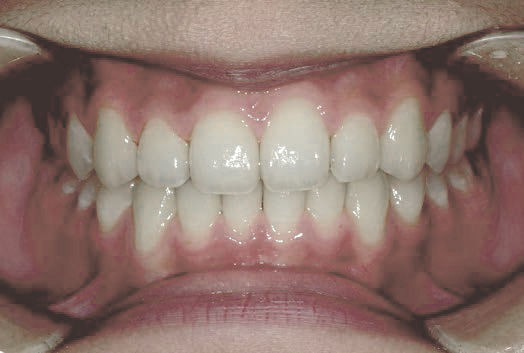

でこぼこ

口呼吸から鼻呼吸、食べ方や飲み込み方で歯並びは良くなる!

Nさん (矯正開始時:8歳)

Before

After

上の前歯がゆがみ下の歯が内側に傾いています。舌の位置が悪く、口を開けたまま食べ物を飲み込む癖がありました。また、口をポカンと開けてテレビを見ていることが多いなど、鼻づまりによる口呼吸特有の症状が見られました。

治療を終えて

装置によって上あごを広げ前歯をきれいに並べました。下の歯の位置も整えました。歯がしっかりと咬み合うようになり、舌の位置や鼻の通りも良くなりました。気道も広がったことで、口呼吸が改善されました。

主訴・治療内容 でこぼこの歯で、将来の歯並びが心配と来院されましたが、呼吸法やお口の使い方が原因と、丁寧に説明させていただきました。

治療期間 2年半

費用 495,000円(税込)